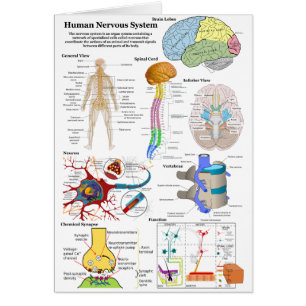

Abbildung des menschlichen Gehirns und des zentral

Sale Preis 4,27 €. Originalpreis 6,09 €.